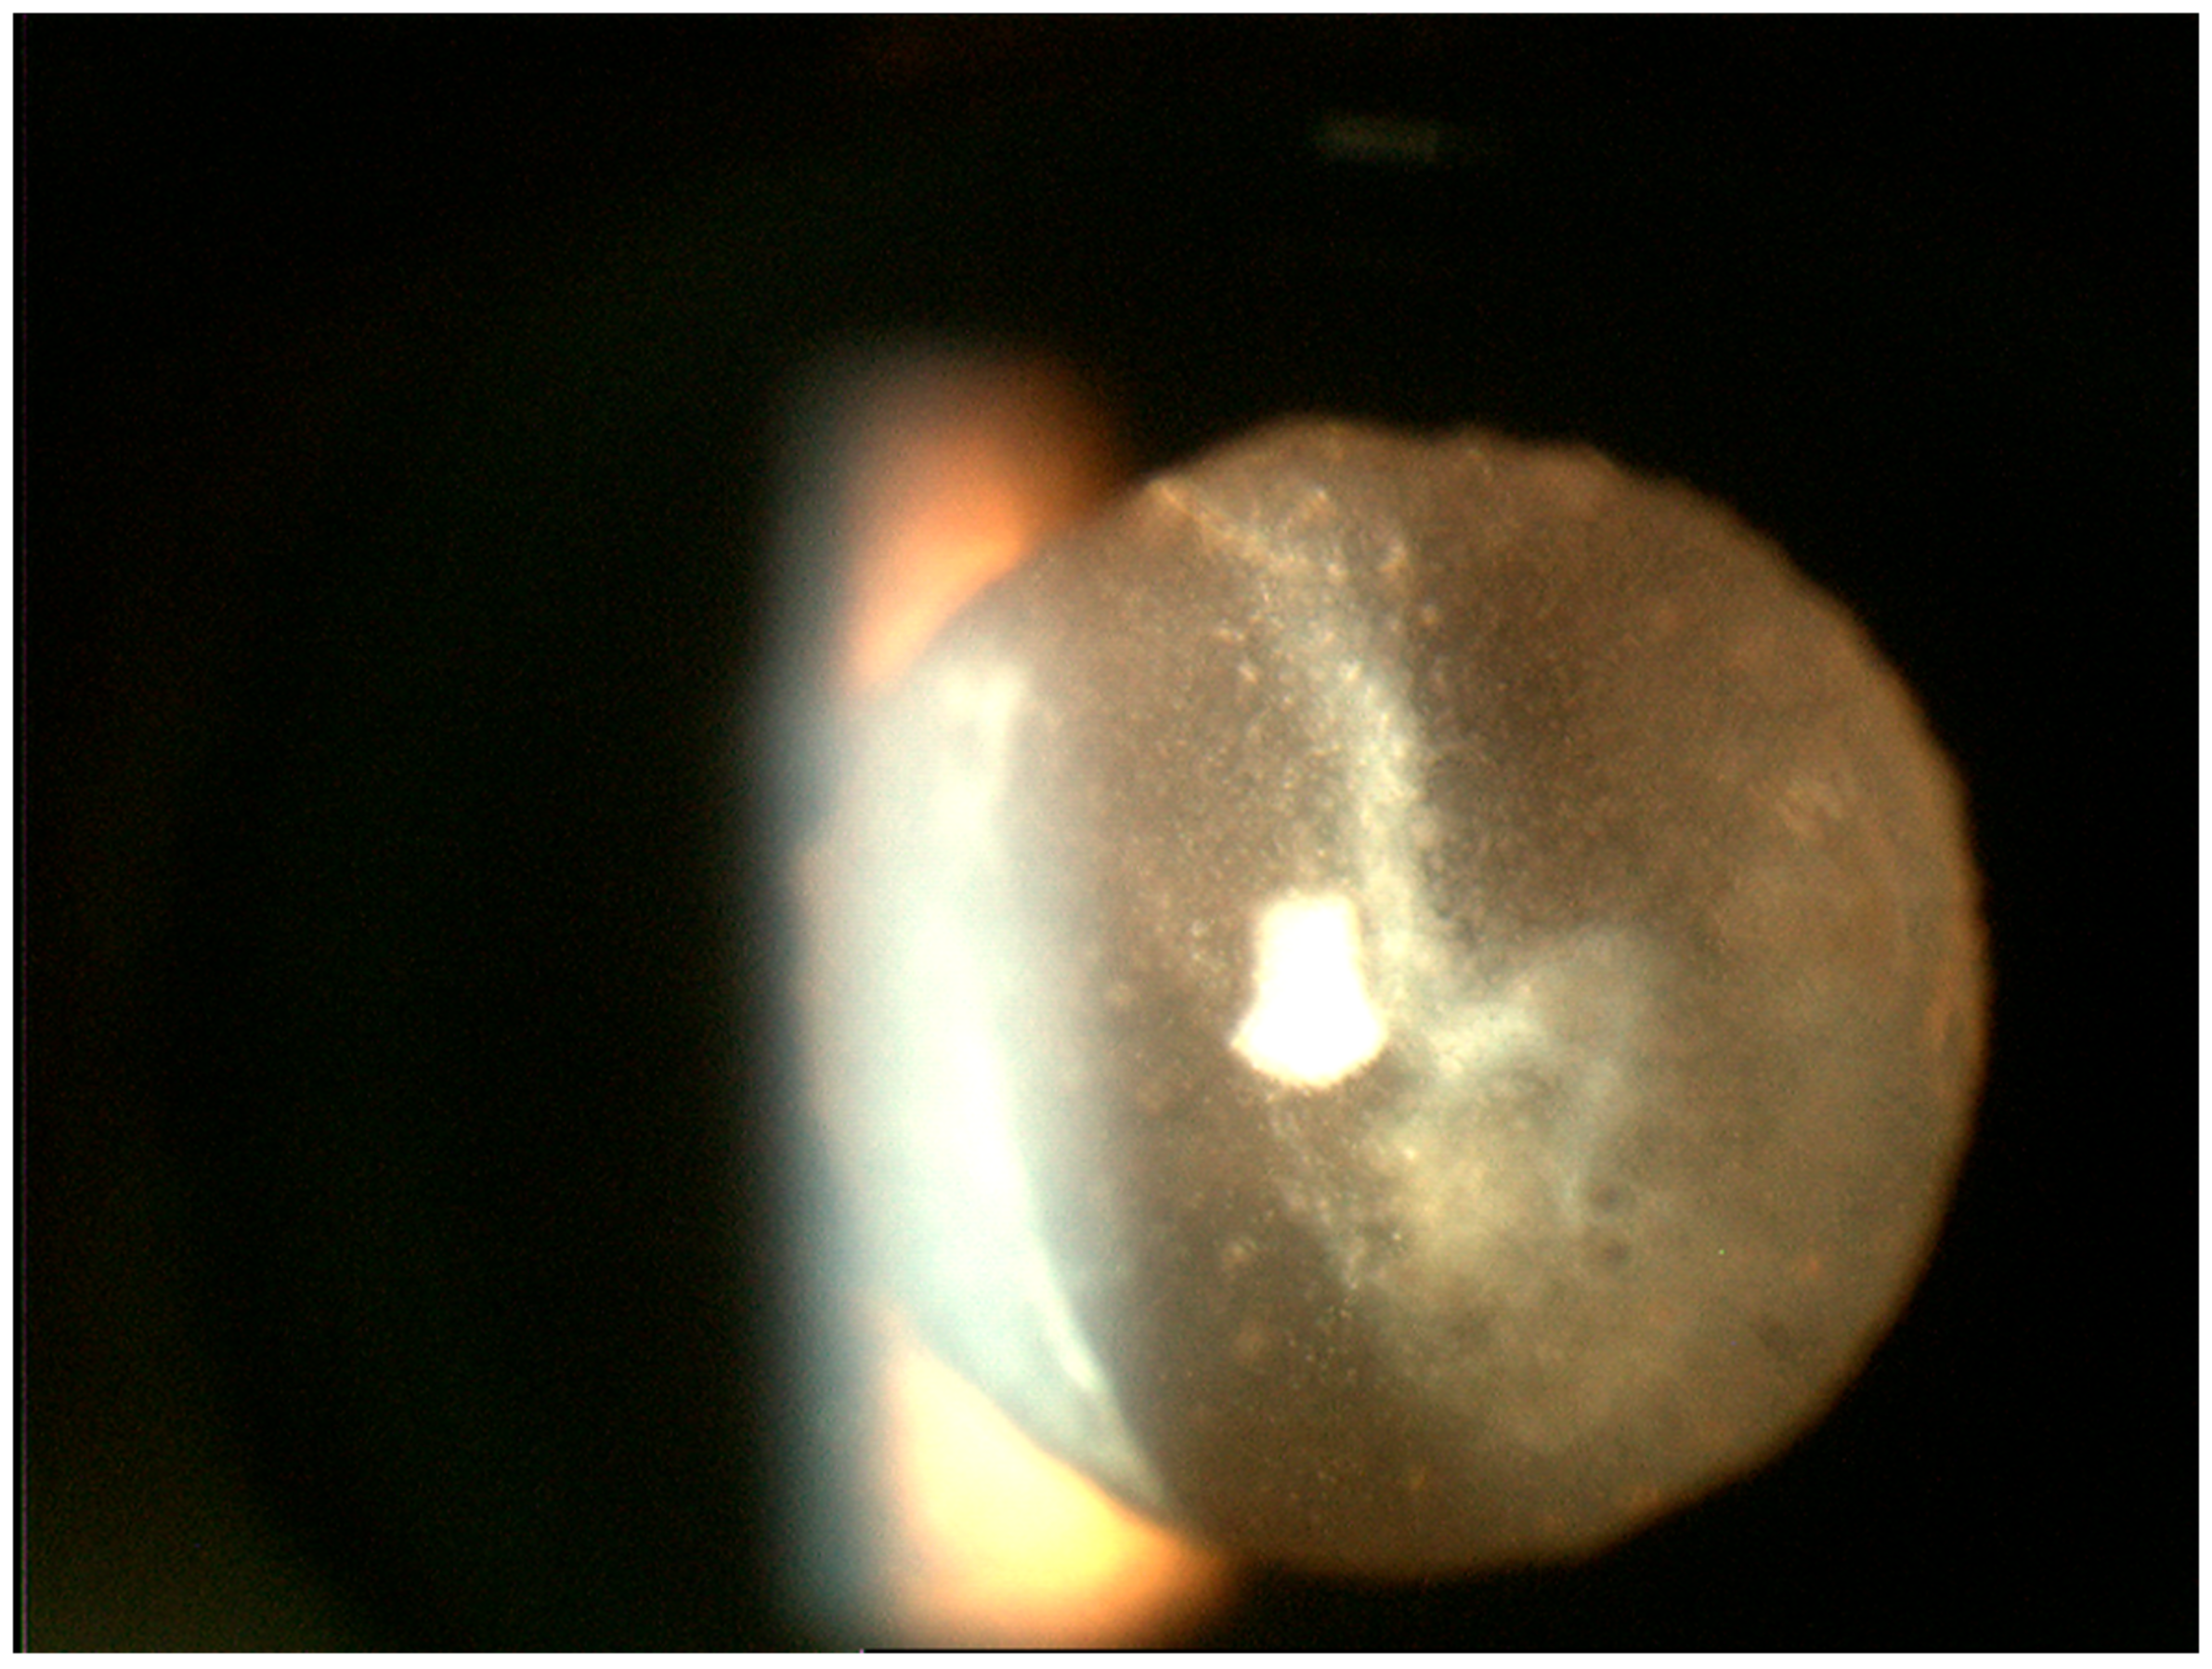

4. Diagnostics

4.2. Ocular Fluid- and Tissue-Based Diagnostics

4.2.1. Cytology and Immunophenotyping